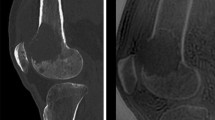

The following morphological variables were assessed for each OO: (a) The bone involved (OObone); (b) for long bones, the segment involved, i.e., the diaphysis, metaphysis, or epiphysis (OOsegment); (c) the location of the nidus center relative to the native cortex (OOcortex), which was used to classify OOs as subperiosteal, intracortical, endosteal, or within the cancellous bone; (d) intra- or extraarticular location (OOarticular); and (e) nidus surface area (mm2) in two perpendicular planes, after using the mouse to delineate the nidus contours on bone-window CT images. The largest surface area (Nidusarea) was recorded (Fig. 2).

3a Computed tomography appearance of a vessel feeding the nidus: Four The CT data were analyzed on bone-windowed images (window width, 3500 HU; window center level, 400 HU) and multiplanar reconstructions. A blood vessel (arrow) was seen as a radiolucent linear or serpiginous groove extending from the cortex and periosteal surface of the bone down to the radiolucent nidus. (a) 15-year-old boy: osteoid osteoma of the femoral metaphysis with a large feeding vessel (b) 34-year-old male: subperiosteal osteoid osteoma of the femoral diaphysis (c) 12-year-old boy: osteoid osteoma of the calcaneus with a single feeding vessel (d) 38-year-old female: osteoid osteoma of the first metatarsal bone. 3b Steps used to measure vessel diameter with ImageJ Subperiosteal OO of the femoral diaphysis in a 12-year-old girl CT images are registered in DICOM format (a). The bone window is inverted to better identify the bone delimiting the vessel (b); a line is drawn perpendicularly to the main axis of the vessel (in yellow). Gray level intensity (coordinate Y) and the corresponding coordinate along this line (X) are used to determine the diameter of the vessel (c). In this example, vessel diameter was 1.25 mm. 3c Determination of the largest vessel diameter (Dmaxvessel) Subperiosteal OO of the femoral diaphysis in a 9-year-old boy Three vessels feeding the nidus are visible. Their diameters (Dvessel) are 1.01 mm, 1.01 mm, and 0.76 mm, respectively. Therefore, Dmaxvessel = 1.01 mm